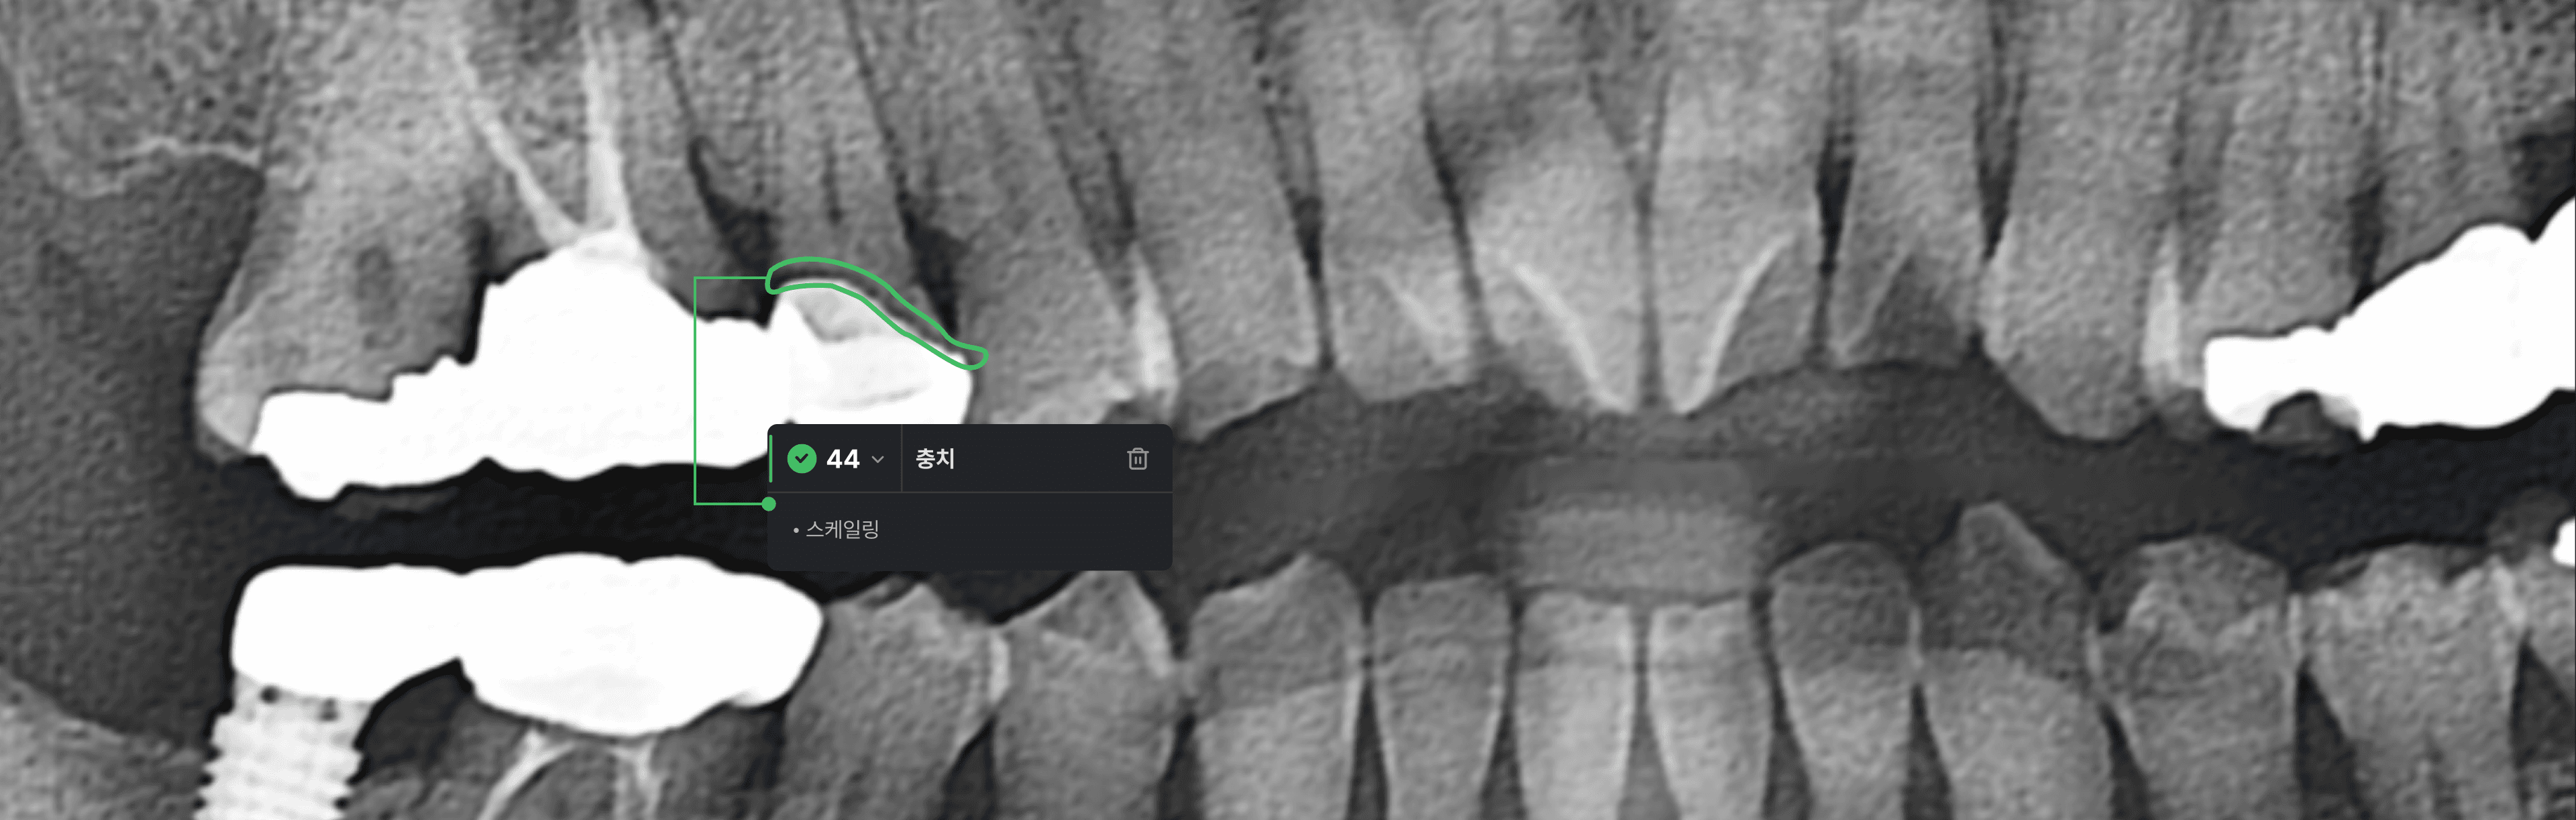

AI 치아정보 탐지

Pano는 인공지능 기술을 활용해 판독시 놓치기 쉬운 세부적인 의심부위를 탐지하고 시각적으로 표기합니다.

X-ray로 찍은 파노라마 영상을 병원 서버에 자동으로 업로드하여, 치과 우식증(Caries), 치근단치주염(Apical periodontitis) 의심 부위와 치조골 레벨,신경 치료, 임플란트, 보철물 등을 실시간으로 표기할수있는 파노를 소개합니다.